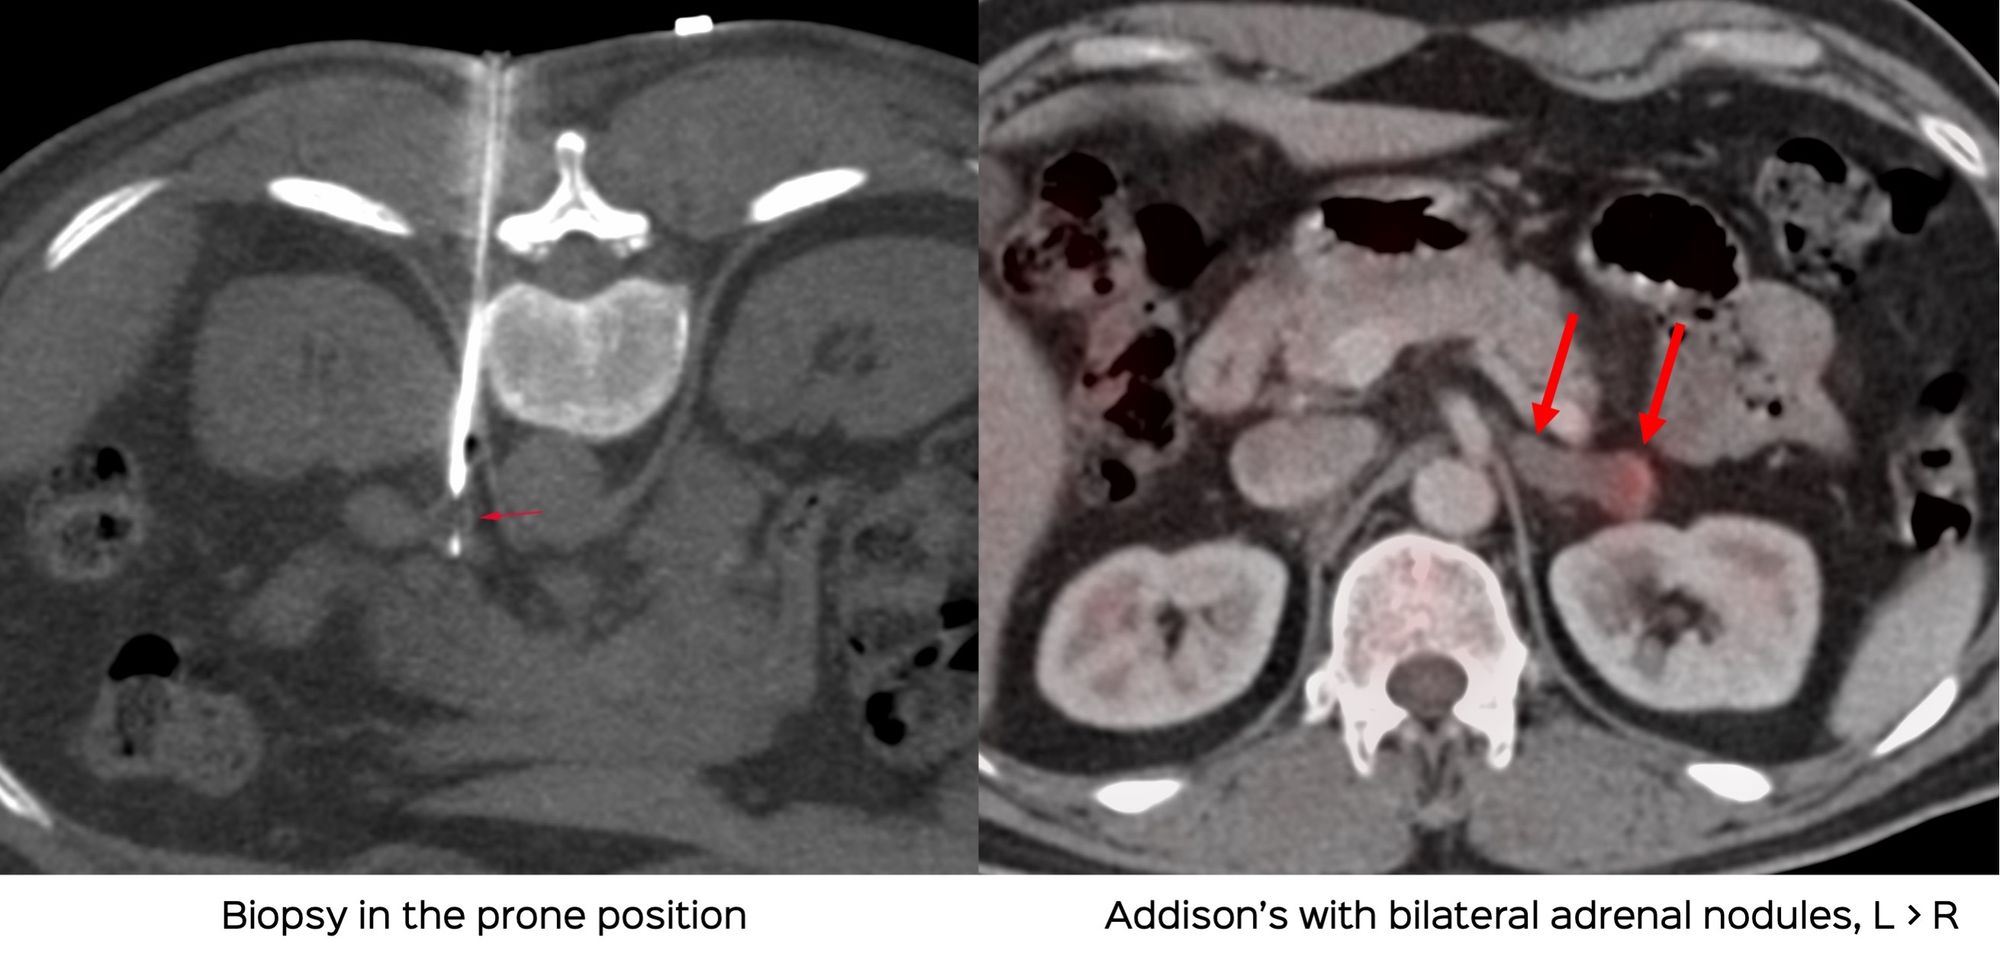

Case 56: Adrenal Gland - Small Nodule Biopsy in the Prone Position

Bhavin Jankharia - 27 August 2021